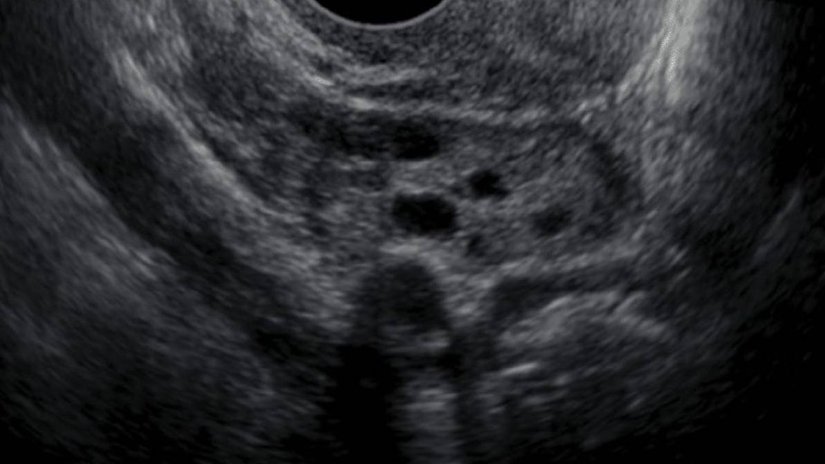

2. Hafta 2D ve 3D Ultrason Görüntüleri

Henüz döllenme gerçekleşmediğinden, ultrasonda bir bebek görmek için çok erkendir. Ancak yumurtalıktaki folikül, ultrasonda görülebilecek boyuttadır.